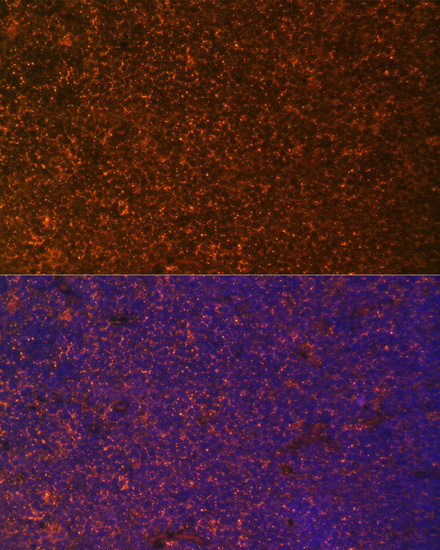

Immunofluorescence analysis of human colon carcinoma cells using TNFRSF25 at dilution of 1:100. Blue: DAPI for nuclear staining.

Immunofluorescence analysis of rat breast cells using TNFRSF25 at dilution of 1:100. Blue: DAPI for nuclear staining.